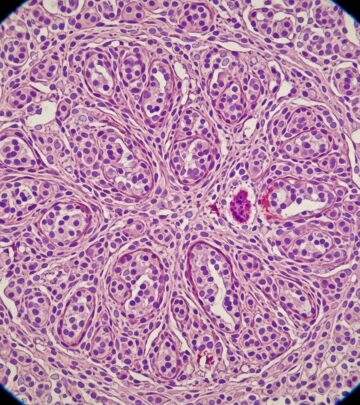

Adenoid Cystic Carcinoma Pathology: A Comprehensive Guide